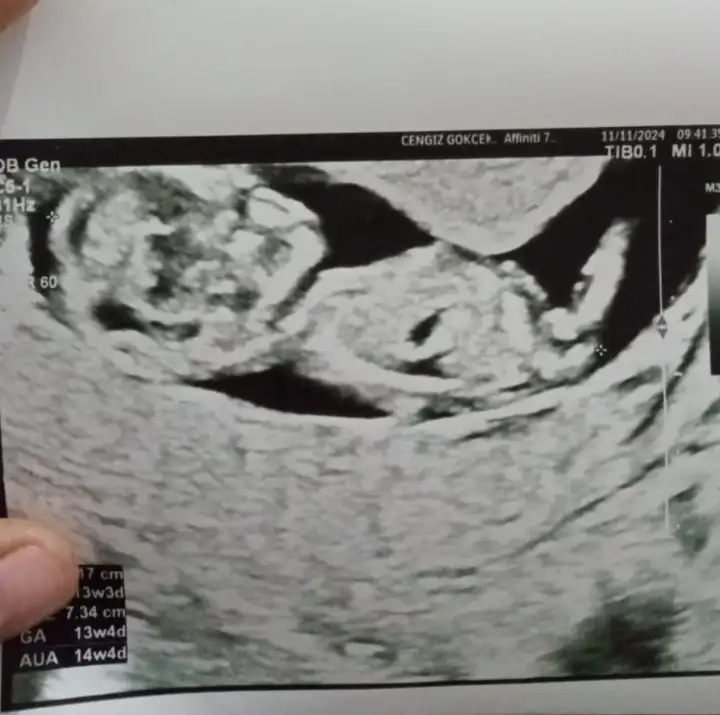

12 haftalık. Doktor bir tahminde bulundu. Kız gibi ama üstten bacak arasına da bakayım dedi üstten bir türlü göremedi. Alt popo tarafından açtı ayağını arası boş dedi. Ama daha küçük 1-2 haftaya netleşir dedi.